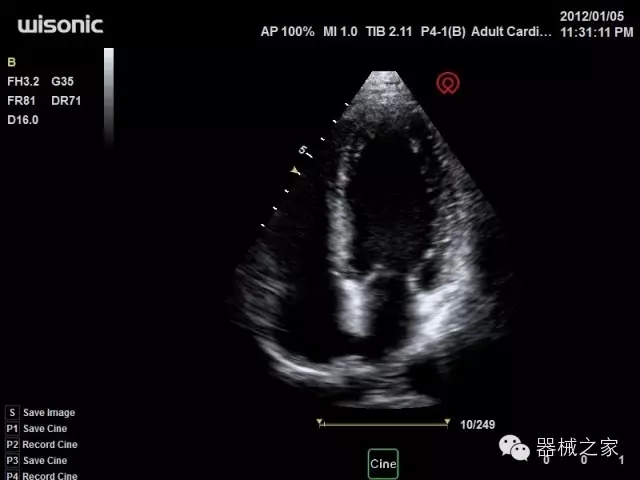

經(jīng)典產(chǎn)品:四葉草

臨床圖片賞析

產(chǎn)品特點(diǎn)

·全球目前唯一一款配備主機(jī)雙探頭接口,整機(jī)重量(含電池)在5公斤以內(nèi)的便攜式彩超;

·IMT血管內(nèi)中膜自動(dòng)測(cè)量:為血管性疾病評(píng)估提供了有效的評(píng)估手段;

·心功能綜合指數(shù)(TEI指數(shù)):用于左、右心室整體心臟收縮舒張功能評(píng)估的測(cè)量方法;

·全方位可調(diào)M型:有利于更好的觀察心腔大小及室壁階段性運(yùn)動(dòng)的異常情況;

·組織多普勒成像(TDI):TDI可定量評(píng)價(jià)心肌運(yùn)動(dòng),判斷是否有局部病變,還可評(píng)價(jià)早期的舒張功能;